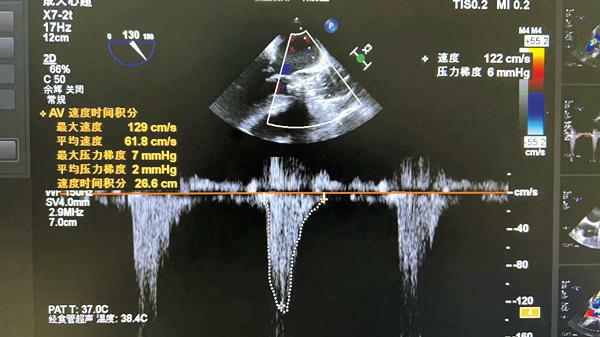

在我院心外科裴斐主任医师,麻醉科刘鹏斌主任医师、罗斌主治医师,超声科韩东刚副主任医师、金鑫主治医师,曹春晖护士长领导的护理团队等多学科协助下,韩振华主任、王新宏副主任医师、刘小军主治医师等先为患者行冠脉造影提示右冠近段95%狭窄(图1),先行PCI干预,右冠植入3.0x22mm支架1枚(图2)。后成功为患者植入TAV24mmVitaFlow瓣膜系统,DSA造影显示主动脉瓣位置良好,未见明显瓣周漏(图3),左右冠脉造影正常,术后即刻心脏超声示最大跨瓣流速129cm/s,最大跨瓣压差7mmHg(图4),顺利结束手术。